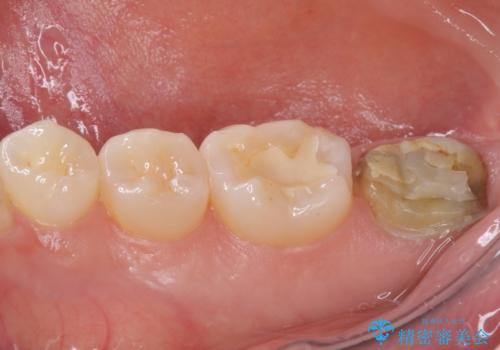

- 奥歯のかぶせものが頻繁に脱離することを気にされて来院された患者様です。

歯の高さが低く、かぶせものを安定して維持させることができないため、歯冠長延長術により歯の高さを増大させた上で、オールセラミッククラウンにて補綴することとしました。

クラウンが外れている期間も長く、虫歯が進行していたため、根管治療も行うこととしました。